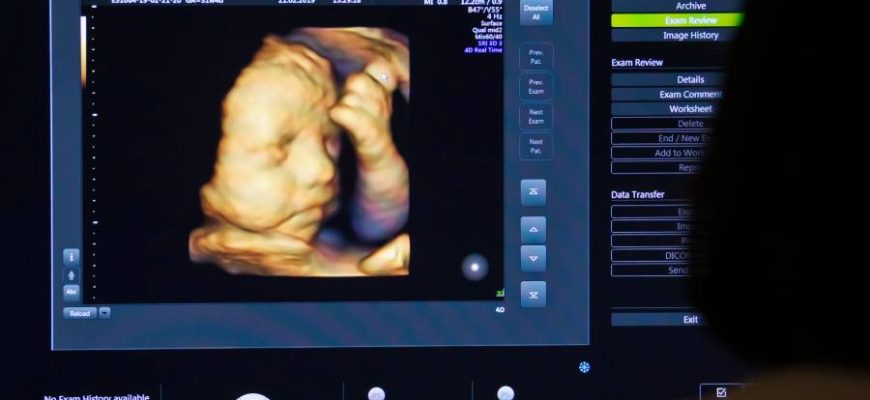

Проблемы качества ультразвукового скрининга: что нужно знать каждому Ультразвуковой скрининг, это одна из самых распространённых и доверенных методов диагностики

Проблемы качества УЗИ-скрининга: что стоит знать каждому? Ультразвуковое исследование (УЗИ) является одним из самых распространённых методов диагностики

Проблемы качества УЗИ: Почему результаты иногда вызывают сомнения и как их улучшить Ультразвуковое исследование (УЗИ) — это один из самых популярных и

Проблемы качества УЗИ: как распознать и устранить ошибки в диагностике Ультразвуковое исследование (УЗИ) является одним из наиболее популярных и доступных

Проблемы качества УЗИ: как распознать и устранить недочёты в диагностике Ультразвуковое исследование (УЗИ), один из самых популярных и широко применяемых